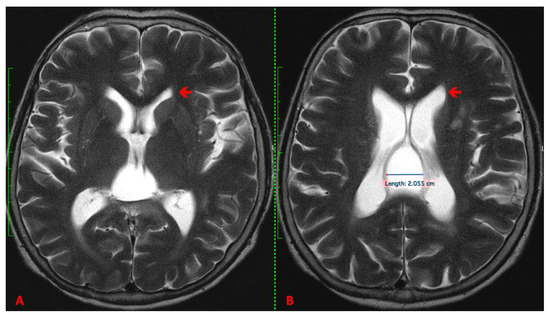

2. Case Report

3.2. Imaging

- T1-Weighted Images: Midline cysts typically appear hypointense (dark) on T1-weighted images.

- T2-Weighted Images: These cysts usually appear hyperintense (bright) on T2-weighted images, reflecting their fluid content.